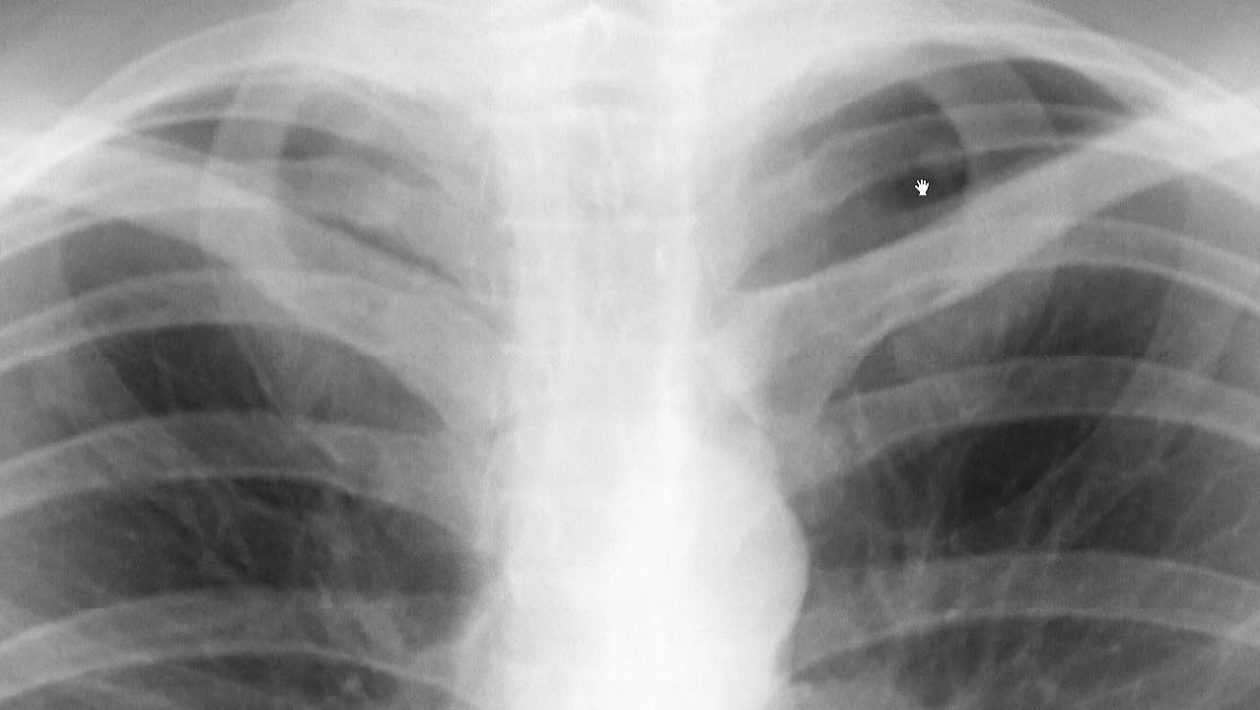

Lääketieteellinen huoli herää, kun tietyt kliiniset kriteerit täyttyvät. Lääketieteellinen tiimi arvioi kyhmyn koon ja ulkonäön, potilaan iän, tupakointihistorian, useiden kyhmien esiintymisen sekä syövän tai asbestialtistuksen esiintymisen potilaan historiassa. Lisäksi aiempien kuvien vertailu voi olla avainasemassa kyhmyn kehityksen analysoinnissa. Tohtori Midtun toteaa: ”Nämä kuvat ovat usein erittäin tärkeitä sen määrittämisessä, onko kyhmy pahanlaatuinen.”

Seuranta- ja valvontastrategiat

Suositukset jatkoseurannasta riippuvat tilanteesta. Jos kyhmyn koko on alle kuusi millimetriä ja potilas ei ole koskaan tupakoinut, lisätutkimuksia ei yleensä määrätä, koska syövän kehittymisen riski on erittäin pieni . Mayo-klinikan tietojen mukaan tällaisissa tapauksissa tarpeeton säteilyaltistus voi olla suurempi riski kuin lisätutkimusten hyödyt.

Jos henkilö tupakoi tai on tupakoinut aiemmin, yleensä suositellaan uuden CT-kuvauksen ottamista vuoden kuluttua. Jos kyhmyt ovat kooltaan kuusi millimetriä tai suurempia tai jos riskitekijöitä on, lääkärit voivat määrätä uusintatutkimukset muutaman kuukauden tai vuoden kuluttua muutosten seuraamiseksi. Joissakin tapauksissa määrätään positroniemissiotomografia (PET-TT) lisätietojen saamiseksi kyhmyn luonteesta.